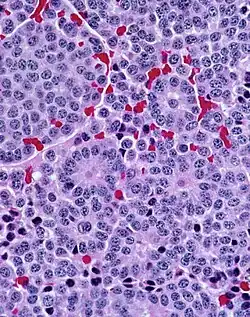

A carcinoid (also carcinoid tumor) is a slow-growing[1] type of neuroendocrine tumor originating in the cells of the neuroendocrine system. In some cases, metastasis may occur. Carcinoid tumors of the midgut (jejunum, ileum, appendix, and cecum) are associated with carcinoid syndrome.

Carcinoid tumors are the most common malignant tumor of the appendix, but they are most commonly associated with the small intestine, and they can also be found in the rectum and stomach. They are known to grow in the liver, but this finding is usually a manifestation of metastatic disease from a primary carcinoid occurring elsewhere in the body. They have a very slow growth rate compared to most malignant tumors. The median age at diagnosis for all patients with neuroendocrine tumors is 63 years.

Carcinoid tumors are apudomas that arise from the enterochromaffin cells throughout the gut. Over two-thirds of carcinoid tumors are found in the gastrointestinal tract.[7]

They were first characterized in 1907 by Siegfried Oberndorfer, a German pathologist at the University of Munich, who coined the term karzinoide, or "carcinoma-like", to describe the unique feature of behaving like a benign tumor despite having a malignant appearance microscopically. The recognition of their endocrine-related properties was later described by Gosset and Masson in 1914, and these tumors are now known to arise from the enterochromaffin (EC) and enterochromaffin-like (ECL) cells of the gut. Some sources credit Otto Lubarsch with the discovery.[10]